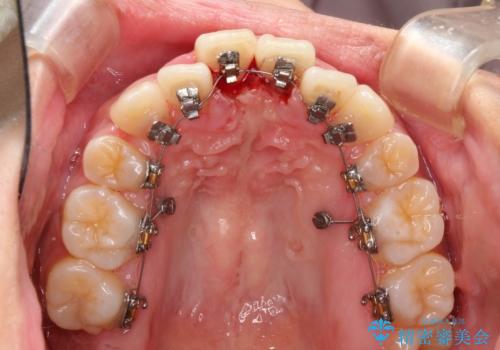

- 上顎の骨格性拡大+両側第1小臼歯抜歯 によりスペースを獲得、フルリンガルによるワイヤー矯正を計画した。

骨格的要因を背景にもつ不正咬合のため、歯列矯正単独での改善は困難と判断しましたが、患者さんとの相談の結果、歯列矯正単独で可能なところまで一緒に頑張りましょうということで、治療をすすめました。

シビアな叢生や開咬も改善することができ、想像以上の改善に時間をかけた甲斐があったと満足していただけました。